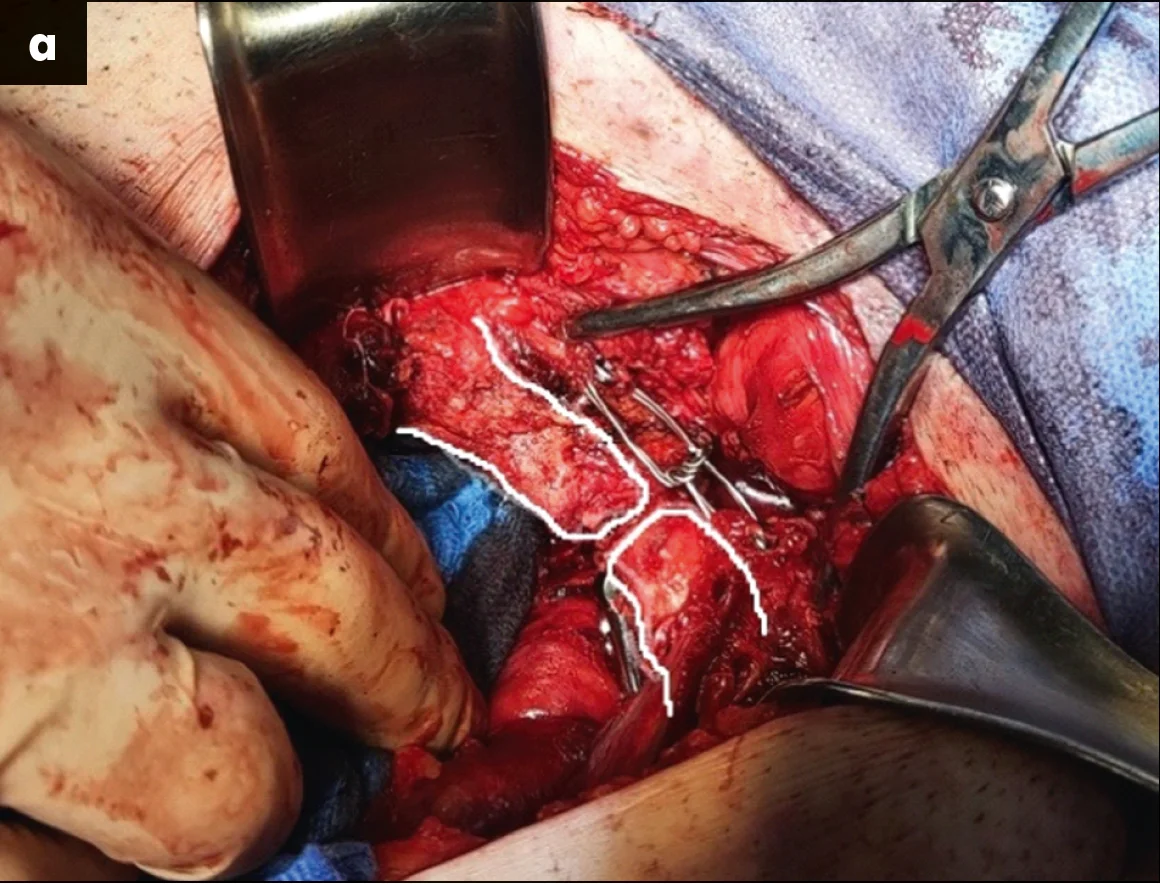

– На четверту добу після отримання травми військовослужбовця було прооперовано під ендотрахеальним наркозом. Найкраще положення пацієнта при такому типі втручання – лежачи на спині, з обов’язковим встановленням сечового катетера. Після проведення первинної фіксації стрижні катетера не видаляли задля використання їх у якості «джойстиків». Було використано заочеревинний нижньо-срединний доступ за Stoppa, проведено ревізію перелому та розриву лобкового симфізу. Першим етапом виконувалася репозиція верхньої гілки правої лобкової кістки. Після репозиції було проведено фіксацію лобкової кістки пластиною по її внутрішній поверхні (рис. 3).

Рис. 3. Виконання першого оперативного прийому з відновлення цілісності тазового кільця: а – репозиція лобкової кістки за допомогою цапки праворуч (стрілками позначено лінію репонованого перелому, білою лінією – контури верхньої гілки лобкової кістки); б – інтраопераційна візуалізація проведеної фіксації пластиною